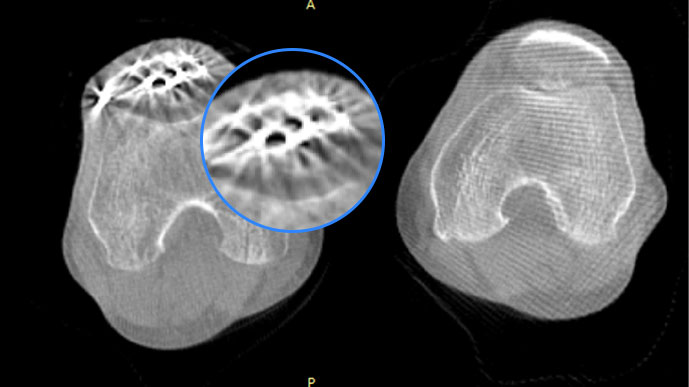

膝關節

關閉金屬偽影校正

開啟金屬偽影校正